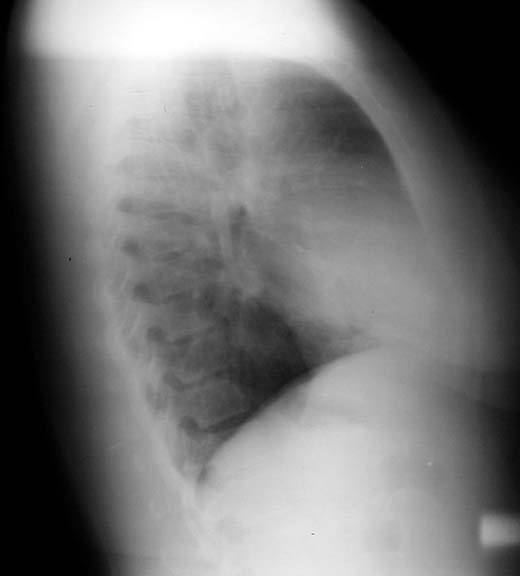

Scimitar Sign

Anamolous pulmonary venous drainage